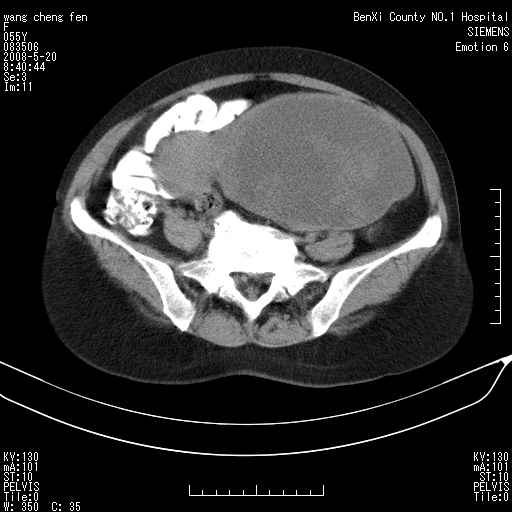

女、绝经后阴道流血3个月

左侧附件区可见一囊性占位,边缘清楚,内可见不规则形软组织影 ce:囊壁及内部可见强化 考虑 卵巢囊腺瘤

左侧附件区巨大囊实性病灶,边缘光整,病灶囊壁较厚,增强示囊壁及实性部分明显强化,强化呈度与宫体实质大致相同,宫腔积液征像,未见盆腔积液等其他异常,考虑左侧卵巢囊腺癌,不除外囊腺瘤及浆膜下肌瘤坏死

左侧附件区巨大囊实性病灶,边缘光整,病灶囊壁较厚,增强示囊壁及实性部分明显强化,强化呈度与宫体实质大致相同,宫腔积液征像,未见盆腔积液等其他异常。绝经后阴道流血3个月,结合病史左侧卵巢囊腺癌首先考虑,宫腔扩大不除外累及。期待结果。

支持浆膜下子宫肌瘤.之前由于网络原因未看全图片,现在重看,宫颈见一类圆形低密度影,增强轻度强化,低于肌层强化,宫腔扩大,考虑宫颈癌伴宫腔积液可能性大.

囊实性肿块分隔厚度较大,厚薄不均,增强实性成分明显强化,有不规则阴道流血,卵巢囊腺癌可能性大。

1,宫颈部占位,宫颈癌?2,左侧附件区囊实性占位,界较清,实质部分强化明显。考虑浆膜下或阔韧带肌瘤囊变可能大。囊腺类肿瘤不除外。